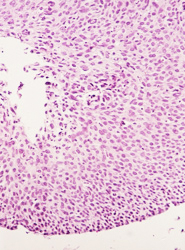

El resultado de una valoración colposcópica de paciente con lesión displásica siempre será confirmado por el estudio histopatológico que realiza el médico anatomopatólogo (estudio de la biopsia tomada en la colposcopía) . A continuación presentamos imágenes histológicas con sus diagnósticos.

• Franca anisocitosis y anisocariosis, hipercromasia y varias figuras mitoticas atipicas en el contexto de las celulas neoplasicas.